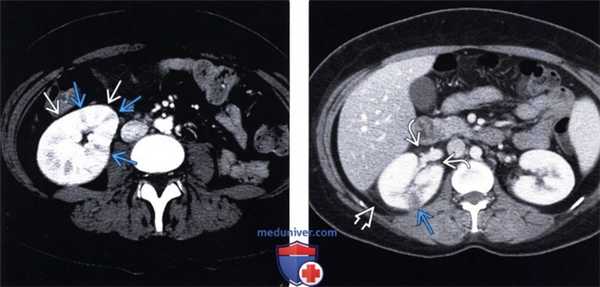

(Слева) КТ с контрастированием, аксиальная проекция, кортико-медуллярная фаза: аномалии левой почки не обнаружены.

(Справа) КТ с контрастированием, аксиальная проекция, экскреторная фаза: у этого пациента выявлено снижение перфузии верхнего полюса левой почки в связи с пиелонефритом.